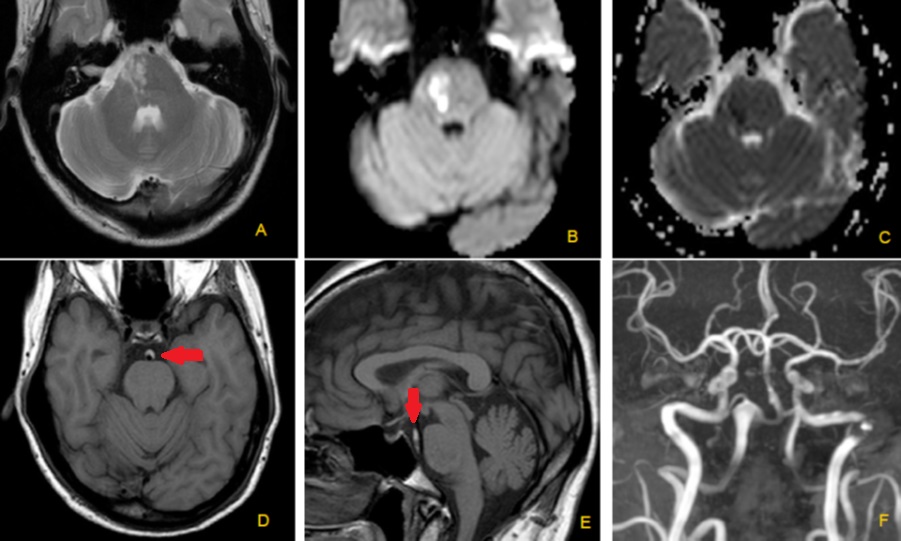

Basilar artery dissection with or without vertebral artery dissection is a rare lesion that can cause intracranial haemorrhage, infarct or mass lesion. We present a case of a middle-aged man with chronic occipital headache and acute hemiparesis. Non-contrasted CT brain shows ectatic right vertebral artery compressing the medulla oblongata and MRI shows acute pontine infarct caused by a basilar artery dissection.